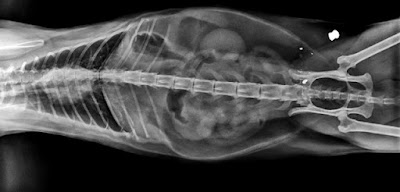

Rápidamente la llevamos al veterinario, donde tuvo que permanecer ingresada para comprobar su evolución y realizar diversas pruebas: toma de tensión, RX, analíticas, ecografía,... también la examinó un especialista cardiólogo, todos los resultados están dentro de lo normal, tan solo la analítica refleja una ligera infección y niveles bajos de potasio.

El diagnóstico es: Ataxia por Síndrome Vestibular, asociado a Síndrome de Horner, pero seguimos sin saber la causa. 😿

RX Eileen (no se aprecia infección oídos)

RX Abdomen normal

(me ahorro lo que pienso del ser que se divierte disparando perdigones a los animales indefensos 😡)